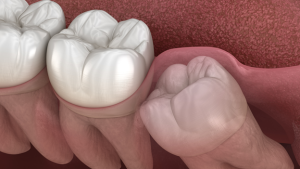

Wisdom Teeth Removal: Answers to Most Common Questions